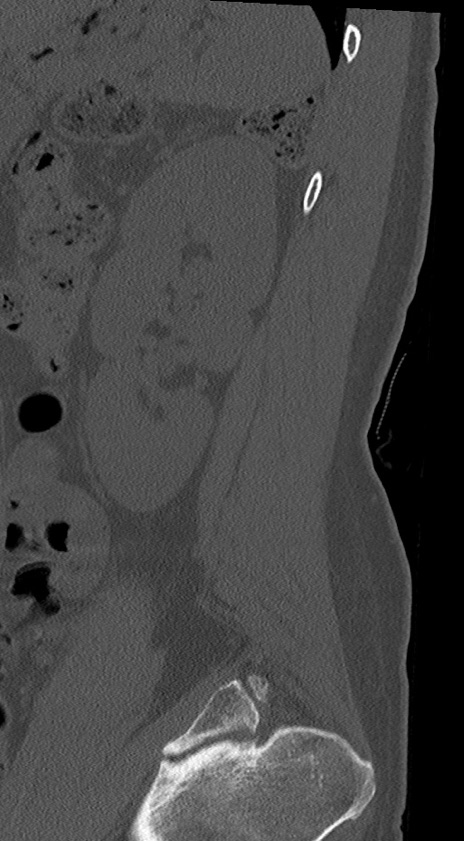

【整形】TIPS症例4 腰椎CT(矢状断像)

腰椎CT

冠状断像